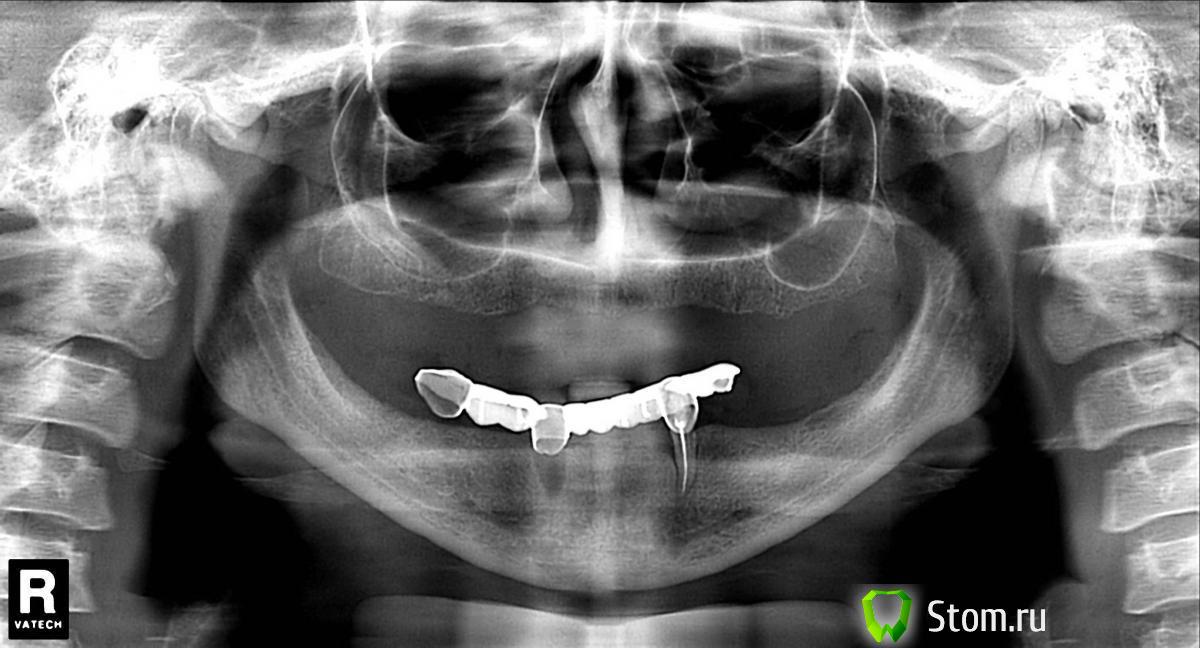

Sahan Опубликовано 26 ноября, 2011 Поделиться Опубликовано 26 ноября, 2011 Пациентка 44 года.Хотел посоветоваться по поводу плана лечения (имплантации) на верхней челюсти.Желание пациента: несъемный протез. Ширина гребня по данным остеометра от 4.5 до 5 мм.Боковые отделы планирую открытый синуслифтинг(СЛ).Вопрос в том ,как лучше делать СЛ справа : ограничиться одним окном или формировать два (пазуха вытянута)?А особенно интересует центральный участок: близко расположенная полость носа. Как быть? Буду благодарен за любые советы.Отдать более опытному коллеге и попроситься ассистировать на операции. Иначе о спокойном сне можете забыть. Ссылка на комментарий

S_81 Опубликовано 27 ноября, 2011 Автор Поделиться Опубликовано 27 ноября, 2011 Внизу Хирургический протокол:4 имплантата , в последующем съемный протез на балке.Верх Хирургический протокал: двухсторонний синуслифтитг ,планируется установка 8 имплантатов Альфа-био(гребень широкий).Протезирование: условно-съемный(на винтах) протез с облицовкой металлокерамикой.План лечения и протезирования давно составлен простом смутило - протяженность правой пазухи(может я ошибаюсь). Я делаю открытый СЛ набором DASK, там стандартные боры,формируют окно примерно 8 мм в диаметре. Сколь мастер-классов я не посещал везде говорят что если пазуха вытянута - не стоит расширять окно более 10 мм,лучше сделать два. Собственно поэтому я и написал.Хотел спросить как кто работает.А ответ: \Sahan. Цитата:Отдать более опытному коллеге и попроситься ассистировать на операции. Иначе о спокойном сне можете забыть.\ - мне кажется не корректным, я не первый год работаю(стаж 18 лет). Если я не корректно задал вопрос можно было так и написать, а не писать ерунду (кто еще кому должен ассистировать,я бы поспорил,да и сон у меня хороший ,я не считаю эту операцию сложной). Ссылка на комментарий

pit Опубликовано 27 ноября, 2011 Поделиться Опубликовано 27 ноября, 2011 Внизу Хирургический протокол:4 имплантата , в последующем съемный протез на балке.Верх Хирургический протокал: двухсторонний синуслифтитг ,планируется установка 8 имплантатов Альфа-био(гребень широкий).Протезирование: условно-съемный(на винтах) протез с облицовкой металлокерамикой.План лечения и протезирования давно составлен простом смутило - протяженность правой пазухи(может я ошибаюсь). Я делаю открытый СЛ набором DASK, там стандартные боры,формируют окно примерно 8 мм в диаметре. Сколь мастер-классов я не посещал везде говорят что если пазуха вытянута - не стоит расширять окно более 10 мм,лучше сделать два. Собственно поэтому я и написал.Хотел спросить как кто работает.А ответ: \Sahan. Цитата:Отдать более опытному коллеге и попроситься ассистировать на операции. Иначе о спокойном сне можете забыть.\ - мне кажется не корректным, я не первый год работаю(стаж 18 лет). Если я не корректно задал вопрос можно было так и написать, а не писать ерунду (кто еще кому должен ассистировать,я бы поспорил,да и сон у меня хороший ,я не считаю эту операцию сложной).Честно говоря, я бы для начала сделал бы КТ, чтоб не тыкать пальцем в небо. И если ситуация соответствует ОПТГ, то сделал бы везде закрытые синусы, возможно слева открытый( от позиций иплантатов зависит). Конкретно по Вашему вопросу сделайте: 2 окна или 1 узкое, но длинное Ссылка на комментарий

S_81 Опубликовано 27 ноября, 2011 Автор Поделиться Опубликовано 27 ноября, 2011 Честно говоря, я бы для начала сделал бы КТ, чтоб не тыкать пальцем в небо . И если ситуация соответствует ОПТГ, то сделал бы везде закрытые синусы, возможно слева открытый( от позиций иплантатов зависит). Конкретно по Вашему вопросу сделайте: 2 окна или 1 узкое, но длинноеСпасибо.Кт есть просто не выложил(на работе). До пазухи слева 4 мм(самая низкая точка), справа3 мм. Ссылка на комментарий